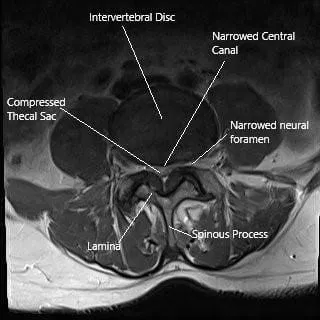

La estenosis lumbar espinal, que a menudo afecta a personas mayores, puede causar síntomas incapacitantes como dolor en las piernas,…